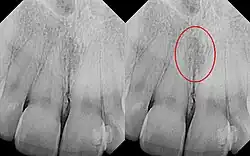

Identical images with heart-shaped radiolucency highlighted in right film.

The nasopalatine duct cyst (NPDC) occurs in the median of the palate, usually anterior to first molars. It often appears between the roots of the maxillary central incisors. Radiographically, it may often appear as a heart-shaped radiolucency. It is usually asymptomatic, but may sometimes produce an elevation in the anterior portion of the palate. It was first described by Meyer in 1914.[1]

As a cyst, the nasopalatine duct cyst requires histological analysis for a definitive diagnosis. Radiographically, the nasopalatine cyst appears as a well-demarcated round, ovoid, or heart-shaped structure presenting in the midline of the maxilla.[6]